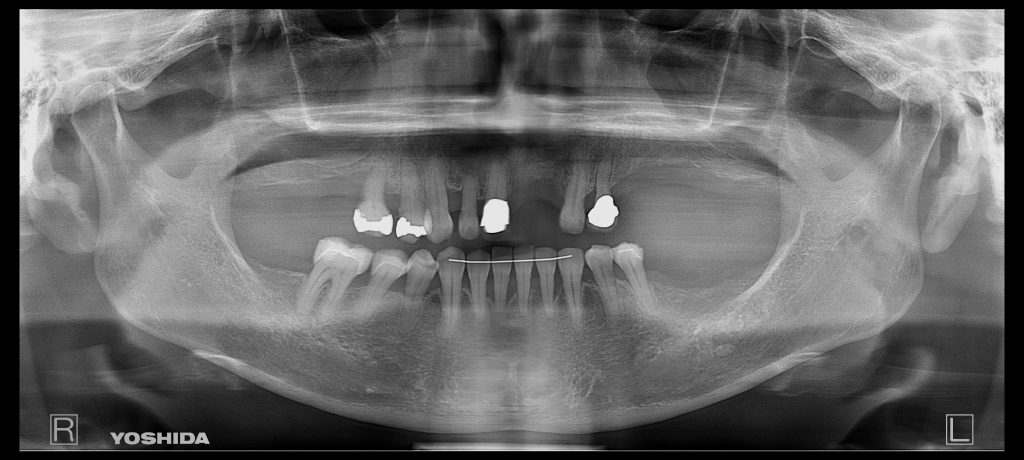

症例130代 女性 歯根破折にて右上6番を抜歯

治療前

ブリッジ・義歯・インプラントの選択肢を提案。

両隣在歯を削り、より負担のかかるブリッジや義歯は選択肢にはなく、両隣在歯を守るインプラントを選択。

骨高不足の為、ソケットリフト(上顎洞洞底膜挙上術)を適用。

オペ後、骨との密着値も良く、約2ヶ月後にはジルコニアを装着し終了。

リスクとしては外科的侵襲がある。デメリットは、保険外診療の為、経済的負担がある。

費用 64万(税込)(オペ・仮歯・最終補綴物まで含む)